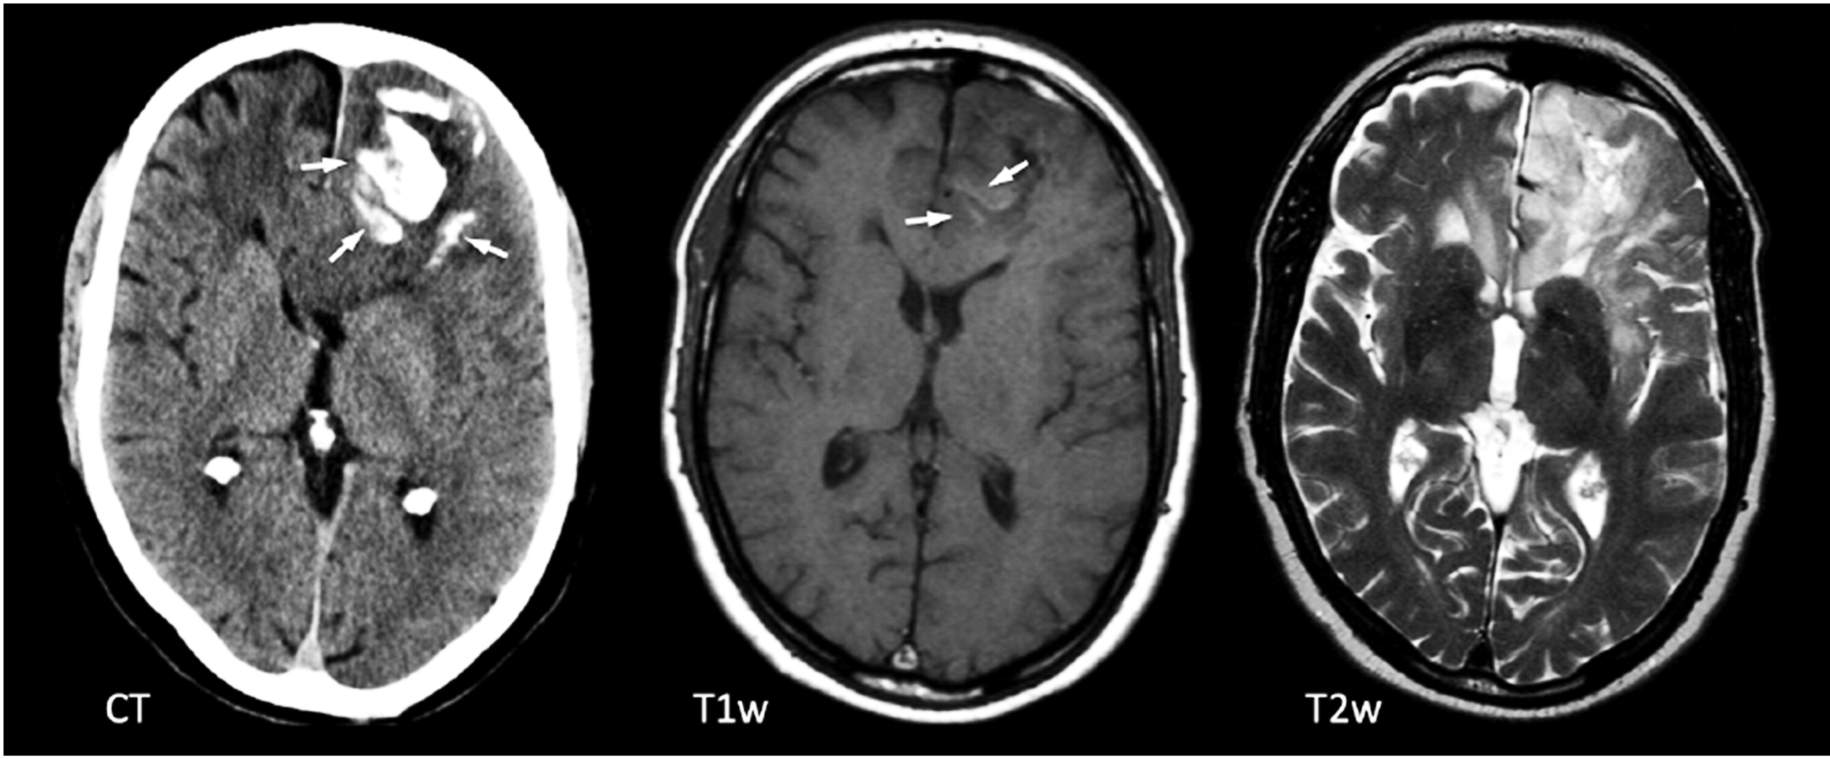

Figura 1: TC (izquierda) y RM (2 imágenes de la derecha) muestran calcificaciones (flechas) en TC en el lóbulo frontal izquierdo, muy características de un oligodendroglioma.

Después de una anamnesis y un examen físico completos, las imágenes del cerebro y la médula espinal pueden identificar posibles tumores. La tomografía computarizada (TC) y la resonancia magnética (RM) a menudo se utilizan para identificar el tamaño y la ubicación del tumor. Las tomografías computarizadas utilizan una serie de rayos X para crear una imagen multidimensional del cerebro. La resonancia magnética utiliza campos magnéticos en lugar de radiación para crear una imagen similar para su evaluación.